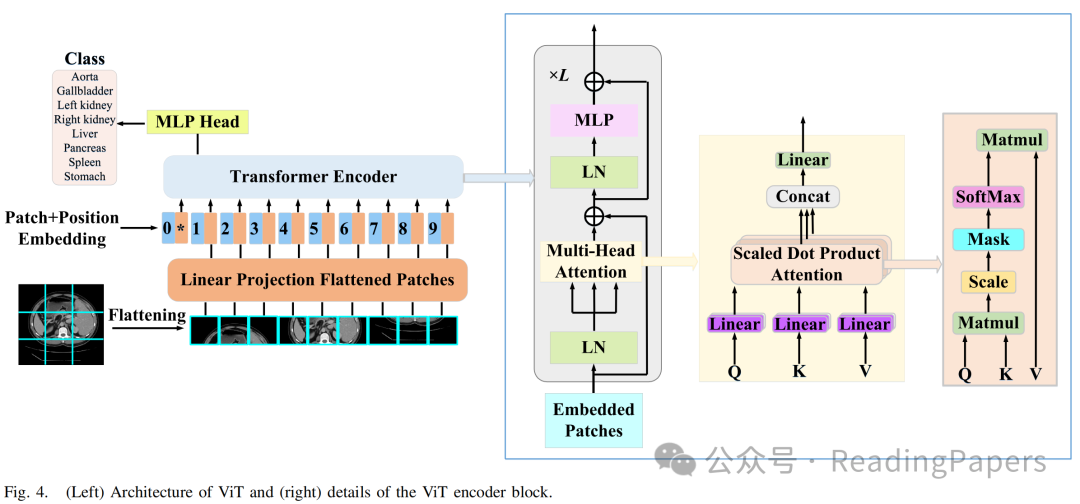

2) Swin Transformer模型

如图4所示,ViT对整个嵌入的图像块进行自注意力计算。典型的MSA模块中的一个主要问题是计算复杂度是图像空间维度的二次函数。Swin Transformer引入了W-MSA和SW-MSA技术来缓解这一限制。图5(b)显示了两个连续的Swin Transformer块,每个块由LayerNorm(LN)层、MSA模块、多层感知器(MLP)层和残差连接组成。此外,两个相邻的MSA块被替换为W-MSA和SW-MSA块。W-MSA的计算开销与图像大小呈线性关系,因为它在定义的窗口内进行自注意力计算。然而,由于这些窗口之间缺乏信息交换,其建模长距离依赖关系的能力有限。相比之下,SW-MSA引入了循环移位操作,将每个窗口向左上方向移动。这一策略使得各种不相邻的子窗口能够有效地相互交互。因此,Swin Transformer能够有效地建模上下文依赖关系并获取高效的分层特征表示。

在Swin Transformer中,输入特征图被划分为不重叠的窗口,每个窗口包含(本文中设置为7)个图像块。作为(S)W-MSA的输入,是一个长度为、维度为的图像块序列。基于这种窗口划分策略,Swin Transformer块的输入和输出可以表示为:

其中,和分别表示第个块的W-MSA和MLP的输出。类似地,和分别表示第个块的SW-MSA和MLP的结果。表示层归一化操作。根据先前的工作,自注意力计算如下:

其中,、和分别表示查询、键和值矩阵;表示查询或键的维度。、和表示三个投影矩阵的可学习参数。此外,表示偏置矩阵。